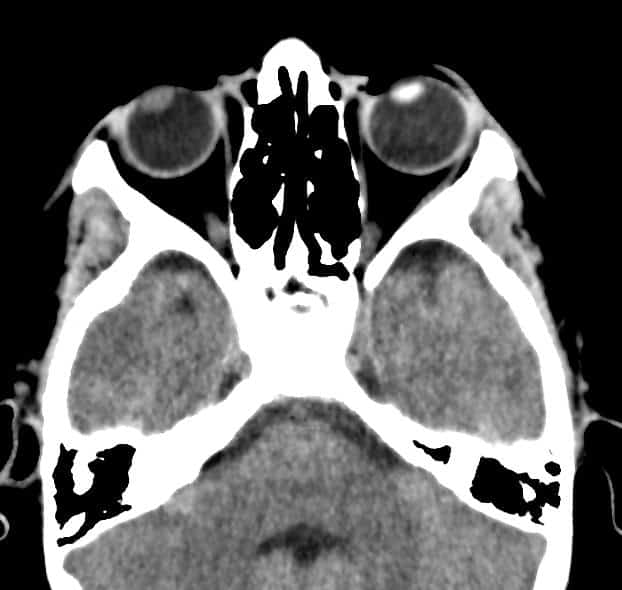

Đục thủy tinh thể trái

Chấn thương nhãn cầu

» Thông tin: Nam giới – 10 tuổi.

» Lâm sàng: Mù mắt phải sau chấn thương.

# Thủy tinh thể phải giảm tỷ trọng do phù nề.